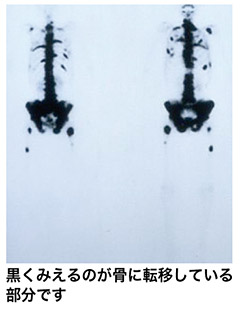

前立腺 癌 骨シンチ. 外部サイトへ whats 前立腺がんを離れます リンク先の第三者のサイトについてのお問い合わせはそれぞれのお問い合わせ先にご連絡くださいwhats前立腺がんはその第三者のサイトの内容等についての責任は負いかねますのでご了承ください. 平成17年3月の人間ドックで前立腺癌が疑われ当時49歳その年の8月に前立腺癌が発見され 9月28日に前立腺癌の手術を受けました当時50歳 前立腺癌はpsa 検査をすることにより確実に早期発見のできる癌ですがその年に私がpsa 検査を受けたのはたまたまその年の検査項目にpsa. 骨シンチで転移したところが真っ黒になっているのを見たときは痛かったが今はホルモン療法でpsaも下がり痛くないので放射線治療は受けないことにした前立腺がんの語り 認定npo法人 健康と病いの語り ディペックス.

今年8月に前立腺癌の生検を受け10本中1本陽性でした グリソンスコア6psa155でした 9月骨シンチを受け1箇所集積があるとの事ただし1箇所である事と呼称は忘れましたがマーカーのような数字が0から1までの間で034と. 骨シンチ 40程に改善 足の痛み違和感ほぼ消える 身体に不都合何もなし 平成12年 4月 psa 05 骨シンチ 腰椎骨盤以外はほぼ消えた 左足は椅子に座っているとしびれの様なものを感じる程度 平成12年.

骨シンチグラフィによる骨転移の診断 Bone Scan Ct Mri画像診断